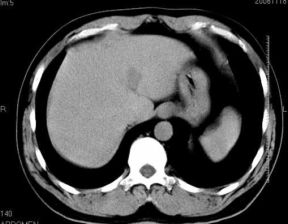

男性,48岁

肝内占位,性质?

肝内多发低密度占位病变,边缘清晰,无强化,肝转移瘤可能

肝内多发低密度占位病变,边缘清晰,无强化,肝转移瘤可能大,请将胃喝水充盈以后再扫描看看,我看大弯侧胃壁较厚。

肝内多发不规则形状低密度灶,强化不明显,考虑转移,积极查找原发灶

患者,男性,48岁

肝内多发低密度类圆形病灶,边缘清晰.增强无强化.

意见:1,考虑多发转移瘤;

2,囊肿与血管瘤不排除.

肝内多发不规则形状低密度灶,强化不明显,考虑转移,找找原发灶

1肝内多发低密度影,考虑:转移瘤 2胃大弯侧胃壁明显增厚,建议胃镜检查除外胃癌

我认为先考虑原发性肝癌。

首先考虑转移瘤。

多考虑转移瘤

转移瘤?